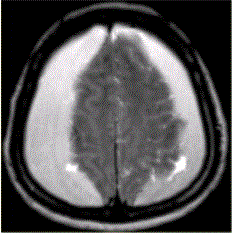

男性,55岁。突发昏迷,MRI表现如下图,可能的诊断是A.硬膜下血肿B.正常C.硬膜外血肿D.脑挫裂伤E.脑脓肿F.脑炎

问题 男性,55岁。突发昏迷,MRI表现如下图,可能的诊断是

选项 A.硬膜下血肿 B.正常 C.硬膜外血肿 D.脑挫裂伤 E.脑脓肿 F.脑炎

答案 A